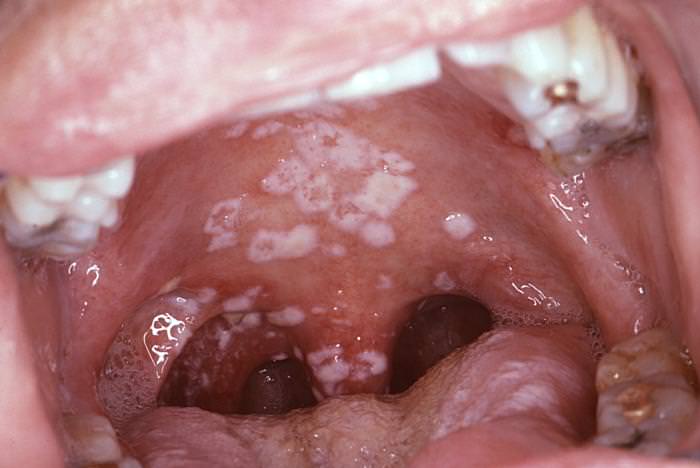

Akut Psödomembranöz Kandidiyazis (Pamukçuk)

Yenidoğanların yüzde 10’unda doğum esnasında annenin vajinal kanalından bulaşma ile oluşabilir.

Pamukçuk plakları kolay kopar, ağızda kalan süt artıkları ile karışabilir ancak kazınması sonrası yerlerinde kırmızı, iltihaplı (inflamasyonlu) bir zemin görülür.

Yetişkinlerde kaşeksi, uzun süreli antibiyotik kullanımı, immünosüpresyon ve diyabet gibi nedenlere bağlı olarak gelişebilir. Normalde tükürük salgısı kandida gelişimini baskıladığı için, ağız kurulukları kandidiyazisi kolaylaştırmaktadır.

Dil, damak, bukkal mukozada beyaz plaklar şeklinde görülür.